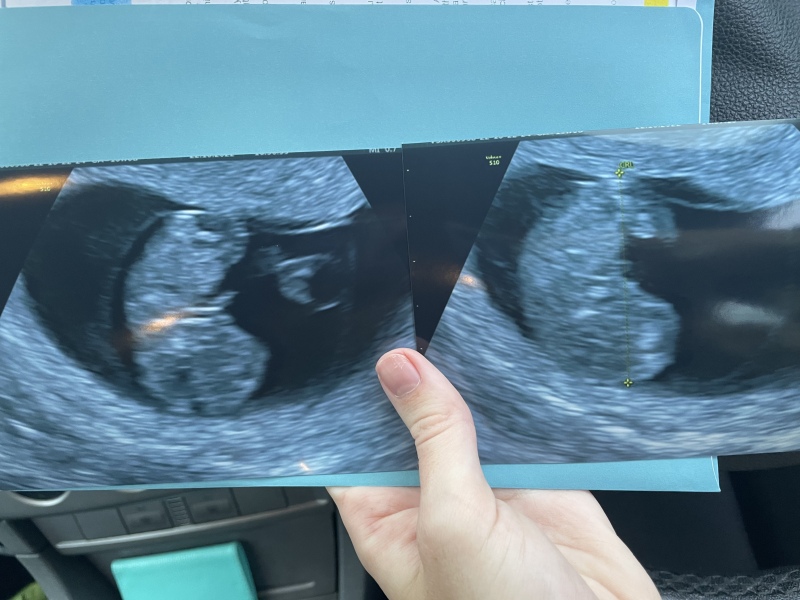

@Cassarat @xalexandra all good! 9week and 1 day everything looks perfect

Very early pregnancy and so much anxiety after miscarriage